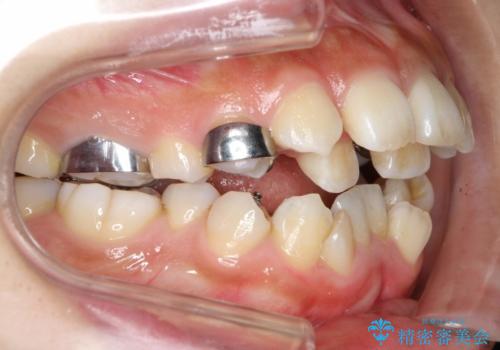

人生が変わる 困難を極める咬合状態に歯列矯正単独で挑戦する

- 上顎の骨格性拡大+両側第1小臼歯抜歯 によりスペースを獲得、フルリンガルによるワイヤー矯正を計画した。

骨格的要因を背景にもつ不正咬合のため、歯列矯正単独での改善は困難と判断しましたが、患者さんとの相談の結果、歯列矯正単独で可能なところまで一緒に頑張りましょうということで、治療をすすめました。

シビアな叢生や開咬も改善することができ、想像以上の改善に時間をかけた甲斐があったと満足していただけました。